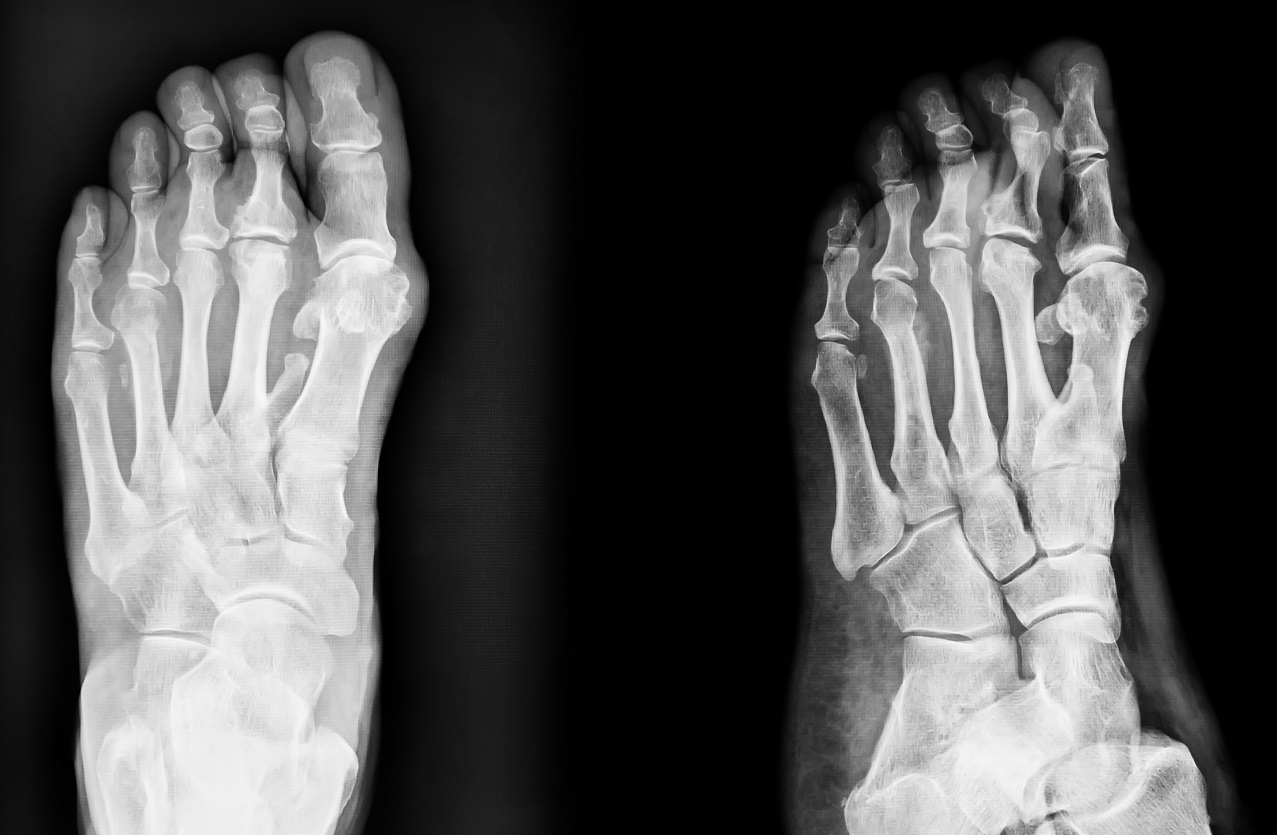

Диагностика травмы пальца ноги

Важно отличить легкое повреждение от перелома или вывиха. На первом этапе доктор собирает анамнез: уточняет обстоятельства травмы, характер боли, динамику симптомов. Далее проводится осмотр — оценивается цвет кожи, наличие гематомы, выраженность отека и подвижность сустава.

Для уточнения применяются инструментальные методы. Рентгенография в двух проекциях позволяет исключить перелом/трещину и оценить суставные поверхности. Если рентген «чистый», но сохраняется выраженная боль или подозрение на повреждение сухожилия разгибателя или внутренние кровоизлияния, могут рекомендовать УЗИ мягких тканей или МРТ. При подозрении на скрытые переломы или оскольчатые повреждения назначается компьютерная томография (КТ). Она особенно полезна при сложных травмах большого пальца.